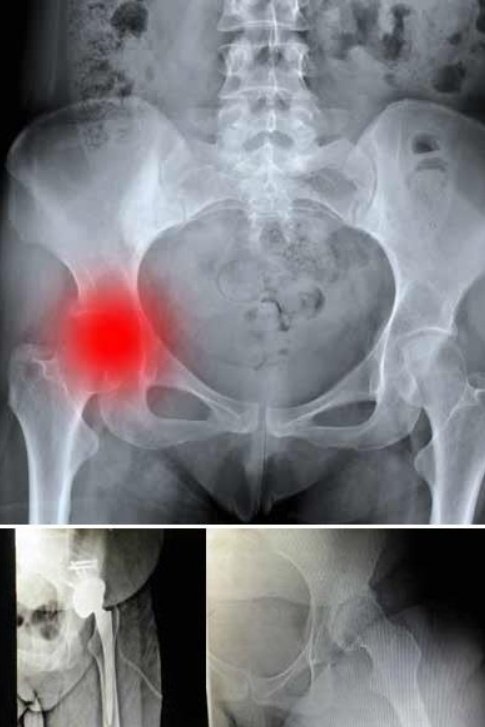

و عادتاً ما يصيب عظام العمود الفقري و عظام رأس الورك "الحوض" و العظام المحيطة بالركبة و الكتف

عادة ما يكون بالفحص السريري الذي يبين وجود الالآم حول المنطقة المصابة و صعوبة حركتها و ضمور العضلات المحيطة بها ، بعد ذلك يتم اجراء فحص الاشعة السينية واشعة الرنين المغناطيسي الذي يظهر فيها مكان الاصابة و شدته ومدى تأثر العظام

اما في الحالات المتقدمة التي لا تستجيب للعلاج التحفظي فقد يلزم اجراء عملية جراحية لإزالة الاعراض

هذه الجراحة تختلف من حالة الى اخرى

مثلاً عندما يكون التآكل في رأس عظمة الورك وهو ما يحدث في الغالبية العظمى فإن التدخل الجراحي لإستبدال نصف مفصل او المفصل كاملاً هو الحل الأمثل ?